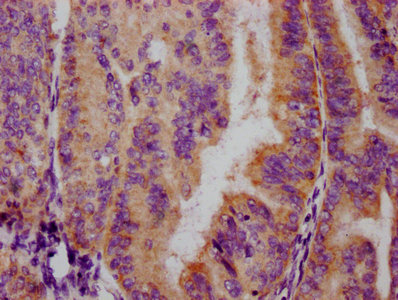

IHC image of CSB-RA008836A253phHU diluted at 1:100 and staining in paraffin-embedded human endometrial cancer performed on a Leica BondTM system. After dewaxing and hydration, antigen retrieval was mediated by high pressure in a citrate buffer (pH 6.0). Section was blocked with 10% normal goat serum 30min at RT. Then primary antibody (1% BSA) was incubated at 4℃ overnight. The primary is detected by a biotinylated secondary antibody and visualized using an HRP conjugated SP system.